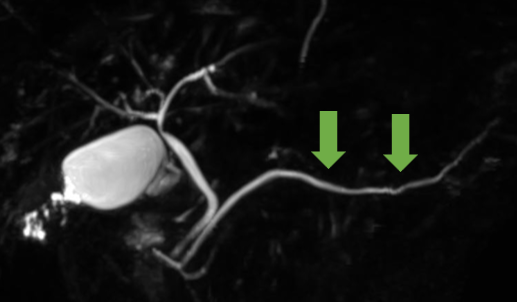

【正常例】膵管の形態を鮮明に描出可能です。